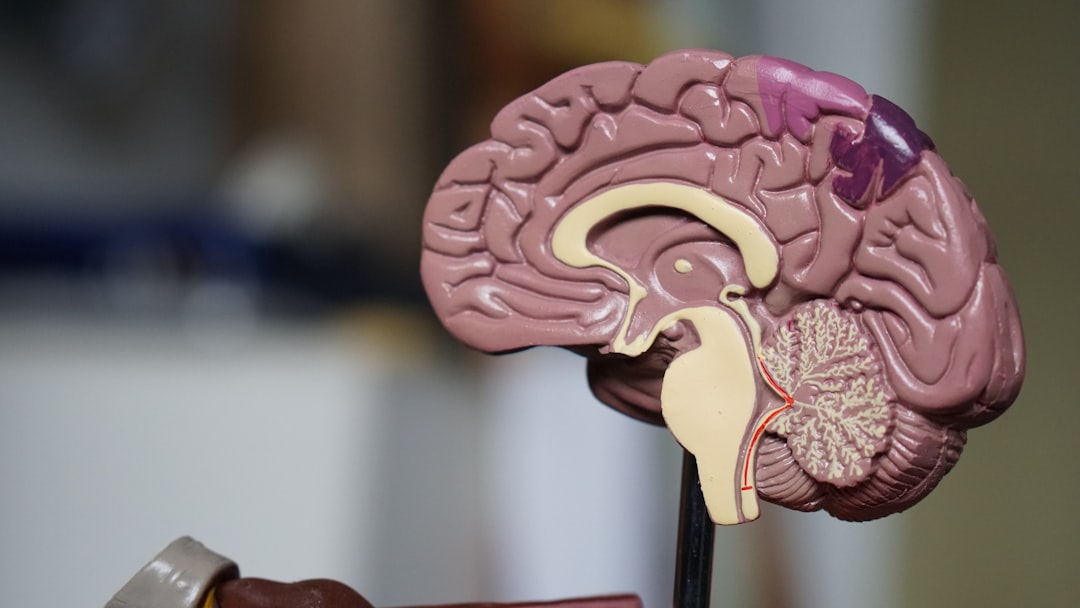

The Link Between Gut Health and Neurotransmitter Production

Gut bacteria are surprisingly powerful when it comes to producing and regulating neurotransmitters. The *Nature Communications* study from 2024 revealed that certain strains of gut bacteria can synthesize GABA, which helps calm the nervous system and reduce anxiety. Other microbes are involved in the production of dopamine and serotonin, both vital for feelings of well-being and motivation. The gut also influences levels of brain-derived neurotrophic factor (BDNF), which supports learning, memory, and neuroplasticity. Disruptions in these gut-driven processes can lead to mood swings, irritability, and even cognitive decline. Researchers are now focusing on how targeted changes to the gut microbiome could offer new hope for treating mood disorders.